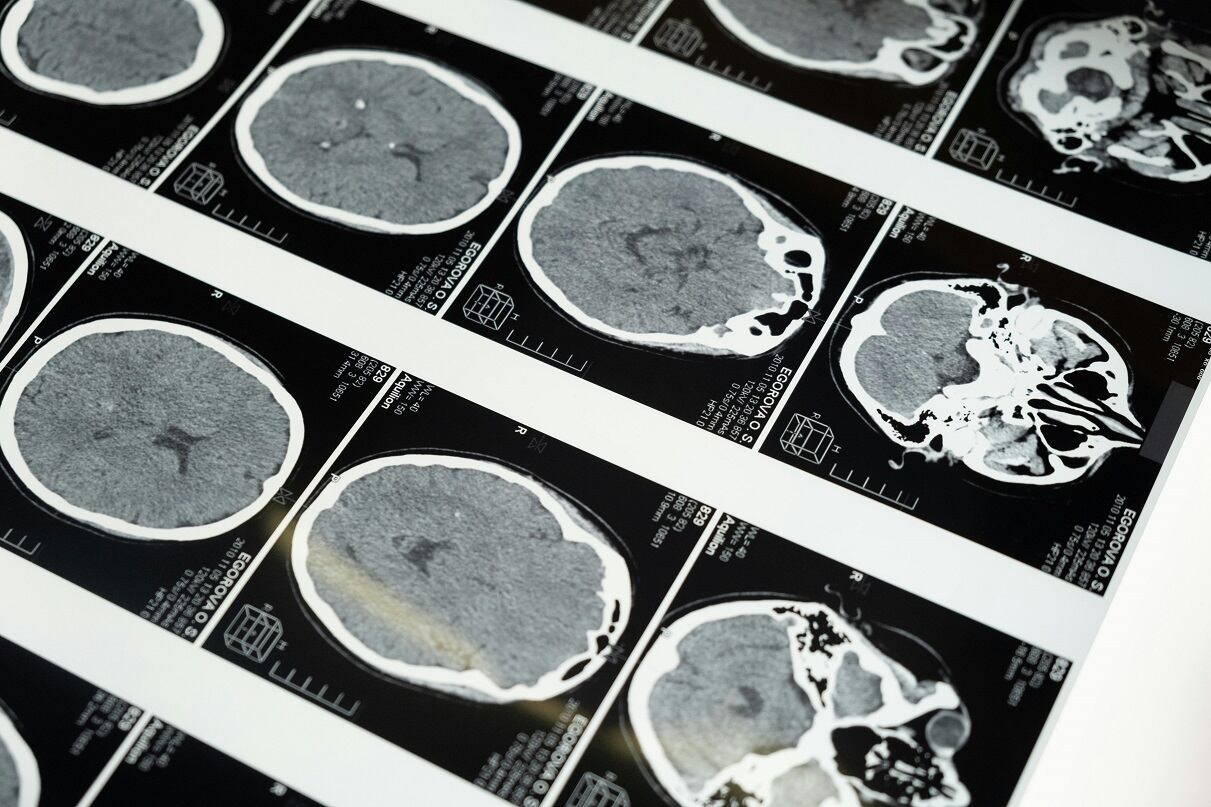

Un equipo de investigadores de Singapur y Estados Unidos descubrió una diferencia biológica clave entre psicópatas y personas comunes. El hallazgo confirma que la psicopatía también se relaciona con el neurodesarrollo.

Científicos hallaron que los psicópatas tienen una región del cerebro más grande, la cual está relacionada con la impulsividad y búsqueda de estímulos